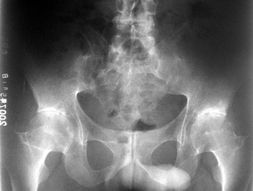

影像学检查

较后要说的就是医院常用的检查方法,那就是对患者进行影像的检查,一般通过X线摄片都能够反应出患者的一些症状,同时,如果患者有骶髂关节炎的话,那么在影片上的显示就是关节面会比较模糊,并且在关节的边缘可能还会呈现锯齿状!患者通过CT、MRI检查,对早期的症状的发现是非常重要的!